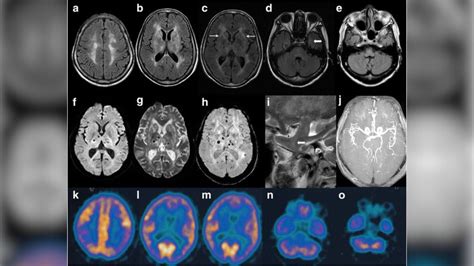

• Neuroimaging: Magnetic resonance imaging (MRI) and positron emission tomography (PET) scans can help identify characteristic brain changes associated with FFI.